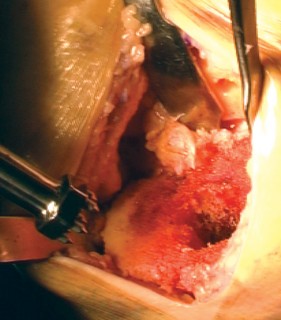

Cementing Technique and Implant Implantation

The hallmark of a cemented TKA is the creation of a durable, interlocking micro-mechanical bond between the host trabecular bone and the polymethylmethacrylate (PMMA) bone cement. PMMA is not an adhesive; it functions as a grout. Therefore, meticulous bone bed preparation is the single most critical factor in preventing aseptic loosening. The resected bony surfaces must be aggressively cleansed using pulsatile lavage to remove marrow, fat, and debris, exposing the porous cancellous bone. Sclerotic areas should be perforated with a small drill bit to enhance cement interdigitation.

The bone must be thoroughly dried immediately prior to cement application. High-viscosity cement is typically mixed under a vacuum to reduce porosity and increase fatigue strength. The cement is applied during its "doughy" phase to both the implant surfaces and the prepared bone. The components are then impacted into place.

Crucially, the cement must be pressurized into the cancellous bone to achieve a penetration depth of 3 to 4 mm. Once the components are seated, all extruded peripheral cement must be meticulously removed with a curette, particularly from the posterior aspect of the condyles and the posterolateral corner, where retained cement fragments can cause severe postoperative pain, third-body wear, or impingement. The knee is then held in full extension with axial compression applied until the exothermic polymerization process is complete and the cement is fully cured.